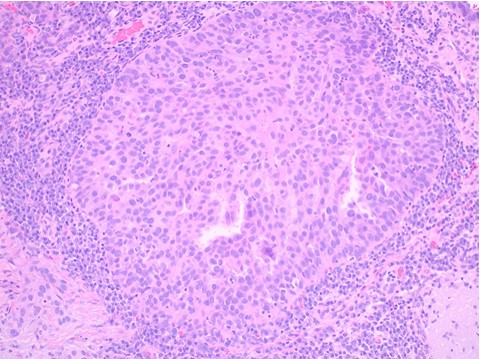

Histopathology: The sections showed a dense superficial and deep perivascular, perifollicular, and interstitial lymphoid infiltrate extending into the subcutaneous tissue. The lymphocytes were pleomorphic, intermediate to large, with irregular chromatin distribution and scattered mitoses. The overlying epidermis demonstrated subtle interface vacuolization with scattered single and collections of lymphocytes, suggestive of epidermotropism. There was no significant necrosis or vasculitis, but extravasation of erythrocytes with riming of fat by atypical lymphocytes was seen.

The histologic differential diagnoses included plaque and tumor stage mycosis fungoides, pseudolymphomatous lupus panniculitis, cytotoxic subcutaneous panniculitis-like-T-cell lymphoma and primary cutaneous gamma/delta T cell lymphoma.

Immunohisochemical evaluation revealed tumor cells to be positive for CD2, CD3, CD56, TIA-1, and granzyme B, and negative for CD5, CD7, CD4, CD8, CD20, and CD123. Additionally, CD 30, Beta FI Gamma M1 were also negative. EBV-encoded RNA (EBER)-1 in situ hybridization was positive for EBV mRNA. RT-PCR T-Cell gene arrangement study was positive.

The histology and staining profile were consistent with EBV positive Extranodal NK/T-Cell Lymphoma.